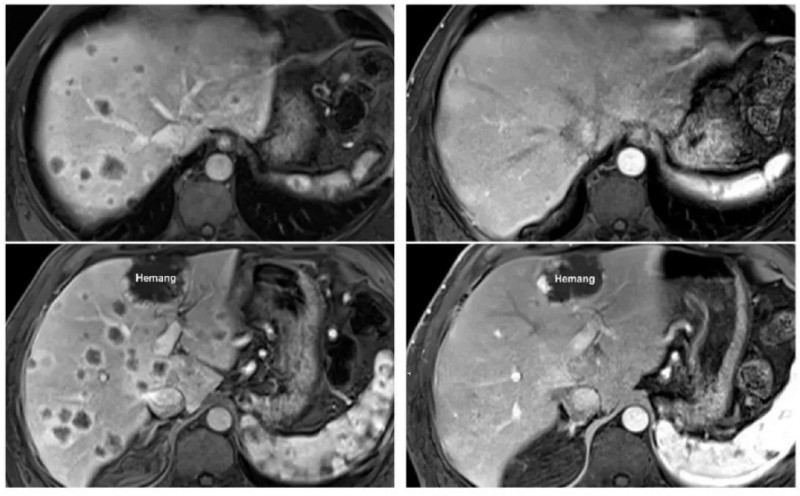

在随访中,有一位患有胰腺癌(被称为癌症之王,致死率极高)且已经转移至肝脏、淋巴结和腹膜的晚期患者。在接受了特定的TIL疗法联合治疗仅仅7个月后,他体内的1个肝转移病灶完全凭空消失,全身整体肿瘤面积大幅缩小了44.1%!

更令人拍案叫绝的是另一位胰腺癌晚期患者,在接受TIL回输后的仅仅6周内,影像学检查震惊了所有的主治医生——他肝脏上密密麻麻的数十个转移瘤,竟然不可思议地全部完全消退!